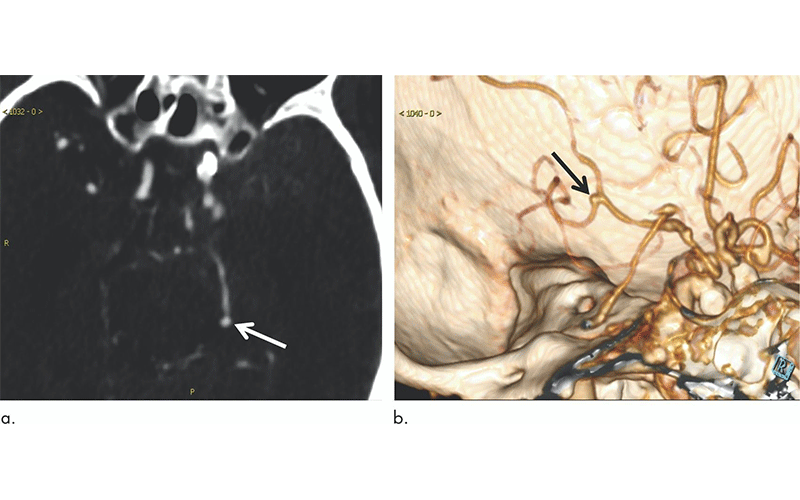

Deep learning (DL) can help physicians detect potentially life-threatening cerebral aneurysms on CT angiography, according to a study published in Radiology.

CT angiography is usually the first choice for evaluating cerebral aneurysms, but cerebral aneurysms can be overlooked on the initial assessment due to their small size and the complexity of the blood vessels in the brain.

The algorithm detected 633 of the 649 cerebral aneurysms for a sensitivity of 97.5%. It also found eight new aneurysms that were overlooked on the initial assessment.

The system has some limitations, Dr. Long noted. It can miss very small aneurysms or aneurysms located close to similar density structures like bones. It also suffers from false positive results, which necessitates careful revision of the system suggestions by human readers.